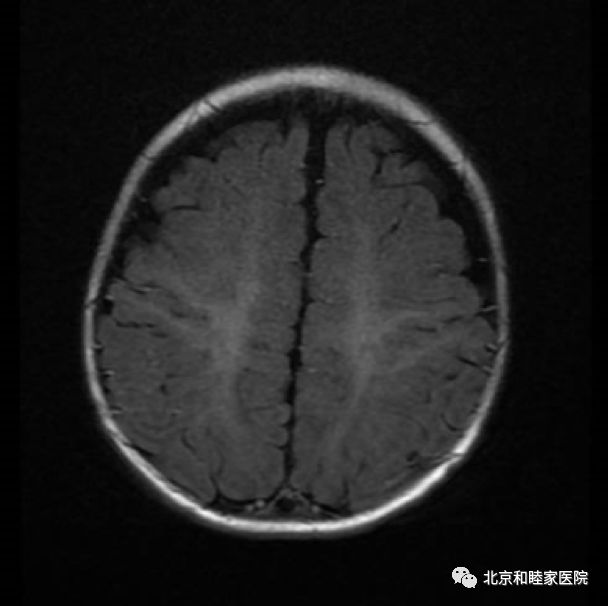

患儿一周后头部MRI影像

患儿两个月后头部MRI影像